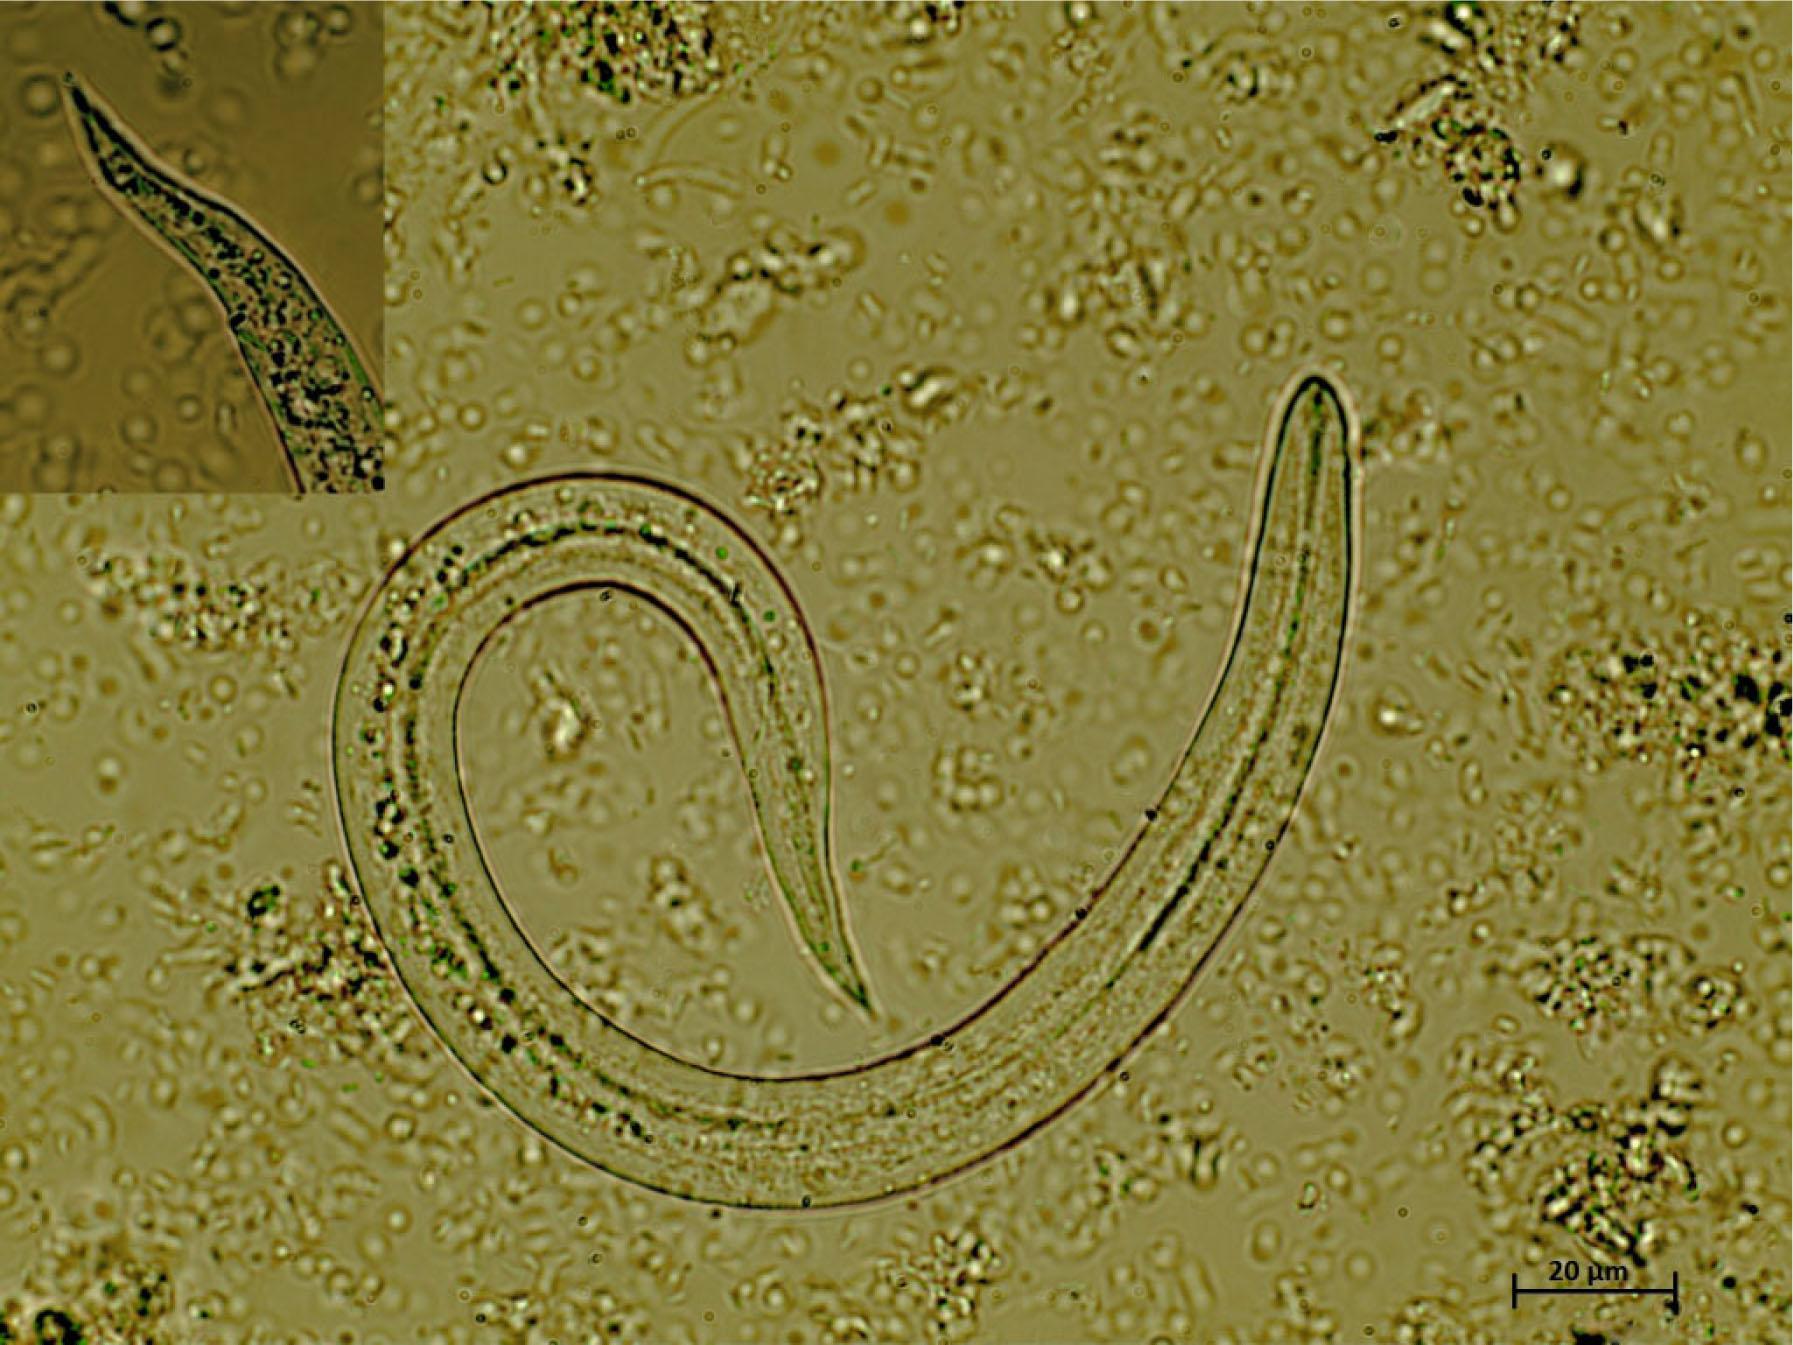

After the visualization of the nematode in the respiratory tract, an enema was performed to collect fresh faecal samples. Qualitative floatation analysis and sedimentation test were negative. The sediment collected from the Baermann apparatus revealed the presence of several motile larvae under light microscopy. A quantitative Baermann was performed, revealing 6066 larvae per gram of faeces (LPG). Several filiform C-shaped larvae were visualized, 260 – 290 μm long and 12 – 14 μm wide, consistent with C. vulpis L1 (Fig. 2). Regarding the molecular identification, the 12S rDNA sequences obtained from the collected larvae (accession no. KR920039) revealed 100 % identity to the nucleotide sequences of C. vulpis available in GenBank®.

Fig. 2

Crenosoma vulpis first stage larvae detected at the Baermann technique, 40x magnification. Note the filiform C-shaped larvae with conical tail, consistent with C. vulpis